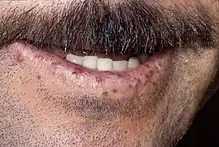

| Characteristic lip telangiectases. | |

Telangiectasias

Telangiectasia (small vascular malformations) may occur in the skin and mucosal linings of the nose and gastrointestinal tract. The most common problem is nosebleeds (epistaxis), which happen frequently from childhood and affect about 90–95% of people with HHT. Lesions on the skin and in the mouth bleed less often but may be considered cosmetically displeasing; they affect about 80%.[1][2] The skin lesions characteristically occur on the lips, the nose and the fingers, and on the skin of the face in sun-exposed areas. They appear suddenly, with the number increasing over time.[2]